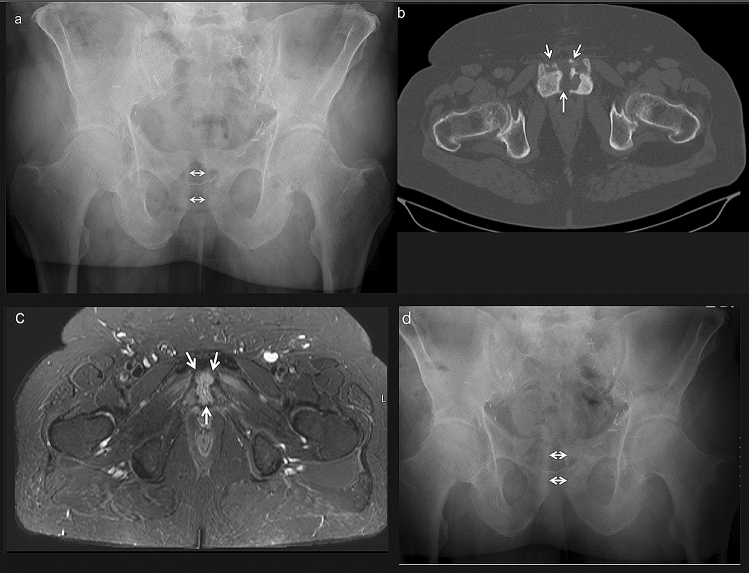

a–d A 69-year-old male with infected pubic symphysitis. Preoperative anteroposterior radiograph of the pelvis showing a slight widening of the pubic symphysis (arrows). Surgical clips of the previous prostatectomy are visible on both sides (a). CT slice of the anterior pelvis shows irregularities of the bony surfaces and necrotic bone fragments in the pubic symphysis joint space (arrows) (b). T2-weighted MRI transection of the pubic symphysis shows a fluid collection in and behind the joint space (arrows) (c). Postoperative anteroposterior radiograph of the pelvis with similar widening of the pubic symphysis as preoperative (arrows) (d)

A 69-year-old, retired male nurse presented with pubic pain, increased during walking. After a cystoprostatectomy, he had constant pubic pain during 3 consecutive years. His body mass index was 39. The cystoprostatectomy had been complicated by a surgical site infection with Pseudomonas aeruginosa that was treated with vacuum-assisted closure (VAC) therapy and systemic antibiotics for 4 weeks. Three weeks before the presentation in our department, pain over the old operation scar had become more intensive. His walking distance was limited to 200 m. Previous treatment with ibuprofen, paracetamol and metamizole had provided no benefit. A widened scar over the symphysis was observed with pubic tenderness. There was no inguinal tenderness with a free range of motion of the hips. A previously performed Tc99 white blood cell scintigraphy showed no increased signalization at the symphysis. Plain radiographs of the pelvis, which were taken at the time of his first presentation in our department, showed a widening of the pubic symphysis (Fig. 1a). A CT scan showed bone irregularities and necrotic bone fragments in the pubic symphysis joint space (Fig. 1b). T2-weighted MRI transections revealed a fluid collection within and behind the pubic symphysis joint space (Fig. 1c). Laboratory tests showed a C-reactive protein (CRP) level of 9.7 mg/L and a leucocyte count (Lc) of 9.01/µL. The patient was admitted, and surgical debridement was performed as described above. Pseudomonas aeruginosa was cultured from the surgical specimens. The patient received intravenous antibiotics for 10 days with clindamycin and was released with a 6-week regimen of oral clindamycin. Follow-up at 6 weeks revealed pain-free walking and no tenderness of the symphysis or the pelvic ring. Between week 6 and 12, the patient was re-hospitalized in our urology department for 3 weeks due to a urinary tract infection with Escherichia coli. The 3 months follow-up showed no remaining symptoms of the pubic symphysis. The clinical followup described above was performed 10 months postoperatively. He had no pain for the four activities and no mobility restrictions at a reported walking distance of 2 km. His mean QoL for the questioned areas was 4.6/5. The plain radiograph of the pelvis after 10 months showed no further widening of the pubic symphysis (Fig. 1d).